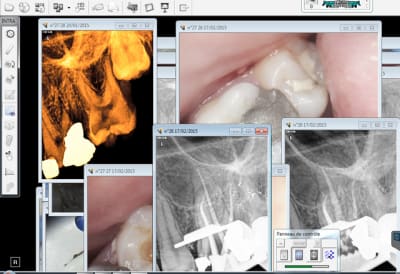

Investis ( si tu peux lol !) dans une camera endo buccale, tu verras il n'y a rien de mieux pour instaurer la confiance.-))))

Personnellement je vais acheter une 2 eme CS 1500, raz le bol de la trimbaler d'un fauteuil à l'autre ! ca commence à faire du bruit question investissements , hein ?

La communication avec le patient, version chicot29.-))))

C'est bien les scellements de sillons et les amalgames juxta pulpaires hein ? surtout jamais de pulpites (26) ni de reprises de caries (27) après quand les indications sont bien posées hein ! ? -))))